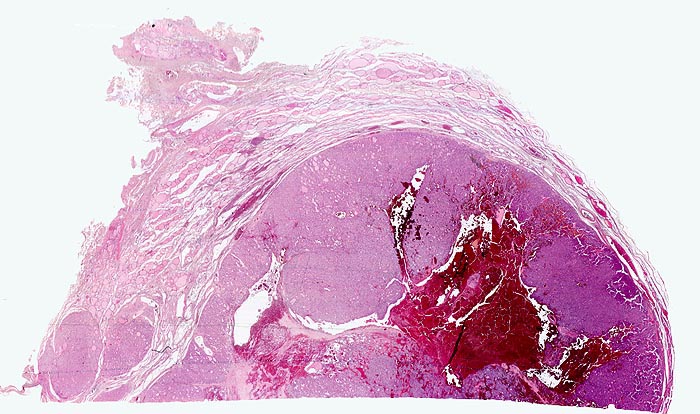

autonomes Adenom

benigner Tumor

Schilddrüse

Scharf begrenzter basophiler Knoten mit angedeuteter Kapsel und zentraler frischer Einblutung. Der Knoten komprimiert das angrenzende Schilddrüsenparenchym. Innerhalb des Knotens sind gar keine oder nur sehr kleine Follikellumina erkennbar. Zwei kleine Knoten mit ähnlicher Morphologie liegen unmittelbar neben dem grossen Knoten.

Die 52-jährige Patientin gibt an, in letzter Zeit vermehrt Herzpalpationen verspürt zu haben. Zusätzlich sei ihr aufgefallen, dass sie nervöser geworden sei, teilweise sogar aggressiv. Sie stellte eine ungewollte Gewichtsabnahme fest.

In der insgesamt eher verkleinerten Schilddrüse ist ein solitärer nicht schmerzhafter Knoten palpabel. Sonographisch kann der klinische Befund bestätigt werden. Die Szintigraphie ergibt eine vermehrte Speicherung von 123-Iodid im Knoten. Freise T3 und T4 sind erhöht, das TSH ist erniedrigt.